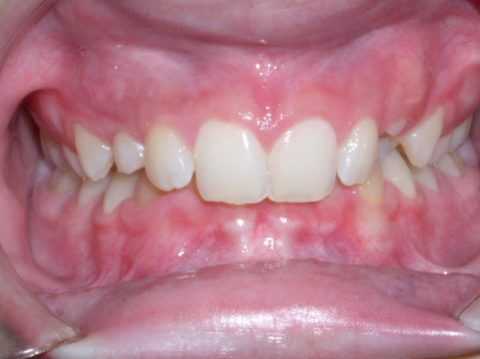

Глубокий прикус - патология ортодонтического характера. Понятие подразумевает нарушение в развитие зубочелюстной системы, при котором верхняя челюсть выдвинута вперед, а ее фронтальные зубы перекрывают зубы нижней челюсти практически на всю высоту коронки:

Глубокий прикус, в первую очередь, это зубная аномалия в переднем отделе. Она может быть как самостоятельная аномалия развития, так и сочетанная аномалия с дистальной окклюзией - то есть с дистальным прикусом, когда у пациента:

Поэтому при глубоком прикусе заметно:

- чрезмерное прорезывание передних зубов,

- в боковом отделе укорочение высоты зубов

В результате пациент получает либо травматический прикус, когда у него бьются нижние резцы в нёбо, либо у него идет смыкание “резец в резец”, но опять же все равно чрезмерное прорезывание фронтальной группы зубов.

Начальная степень глубокого прикуса выражается образованием небольших эстетических дефектов передних зубов - трещинки, мелкие сколы эмали.

Глубокий прикус средней тяжести - интенсивное стирание эмали на внутренней стороне верхних зубов и на внешней стороне зубов нижней челюсти.